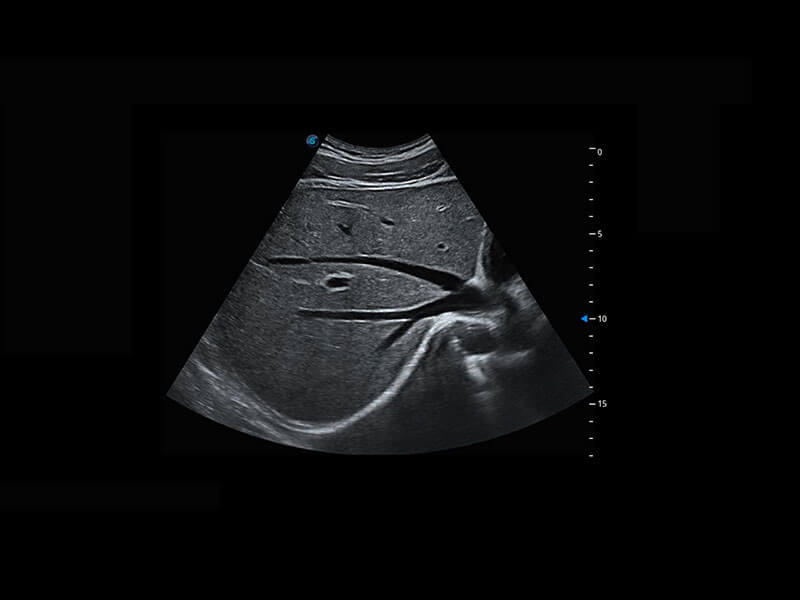

新生儿心脏

P60搭载宽频带线阵探头、宽景成像、弹性成像技术,为您提供乳腺应用方案。P60支持高频相控阵探头、线阵探头、腹部高频探头、腹部微凸探头等,丰富的探头群搭载敏感的彩色血流成像,适用于新生儿多种脏器检测要求,满足新生儿筛查需求。